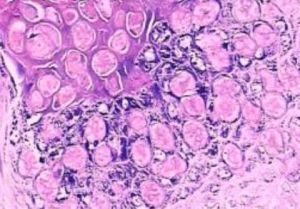

特徵性的是表皮細胞內出現多數細胞質內包涵體,稱為軟疣小體。其小體擠壓每個受損細胞的細胞核,使胞核呈彎月狀,位於細胞的邊緣;軟疣小體由嗜伊紅變成嗜鹼性,在角質層可見多數35μm直徑大小的嗜鹼性軟疣小體,若中心的角質層破裂,排出軟疣小體,形成有中心的火山口樣。毛囊性傳染性軟疣,真皮內有多數擴大的毛囊,其中充滿了軟疣小體。